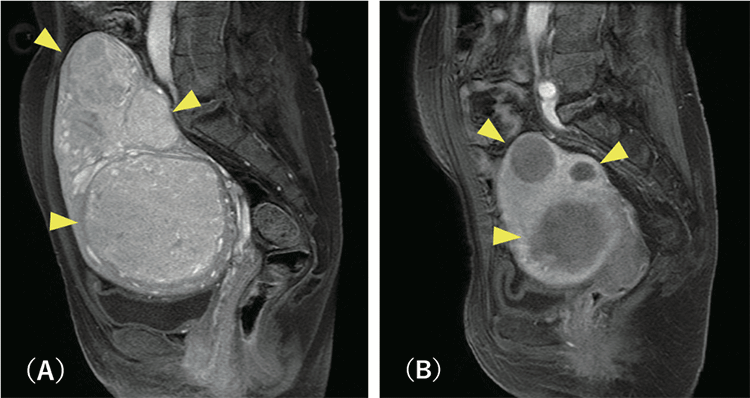

塞栓物質を注入して子宮動脈を詰まらせると、直後より筋腫の細胞は死んでいきます。筋腫への血流が消失したことで、治療した筋腫は数か月かけて徐々に小さくなっていきます(図3)。筋腫が縮小するとともに月経時の出血量も減少し、貧血や圧迫症状も改善していきます。

(A)治療前 (B)UAEより6か月後

黄色矢印で示しているのが子宮筋腫。この患者さんは、これら多数の大きな筋腫によって腹満感と腰痛に悩まされていました。治療前の子宮のサイズは20cmを超えています。UAE治療後、筋腫の血流は消失し、子宮は10cmまで縮小。症状もなくなりました